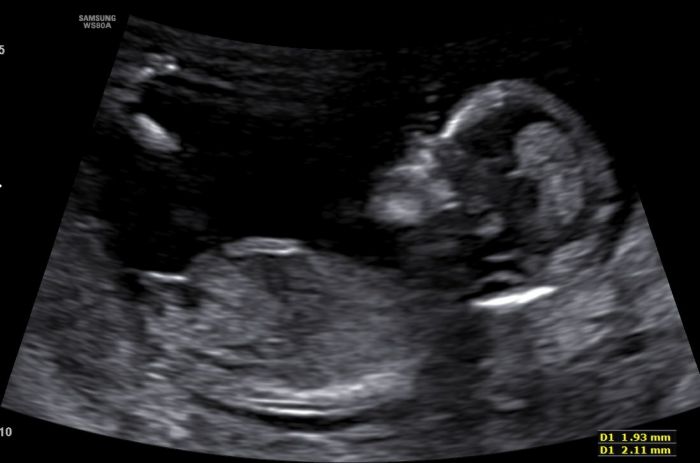

Ahojky, dnes jsem byla na 1. screeningu v Gennetu, vse zatim ok. NT 2,1 mm, riziko na T21 1:7950 a na T13 a 18 1:50000. Dle veku 1:680.